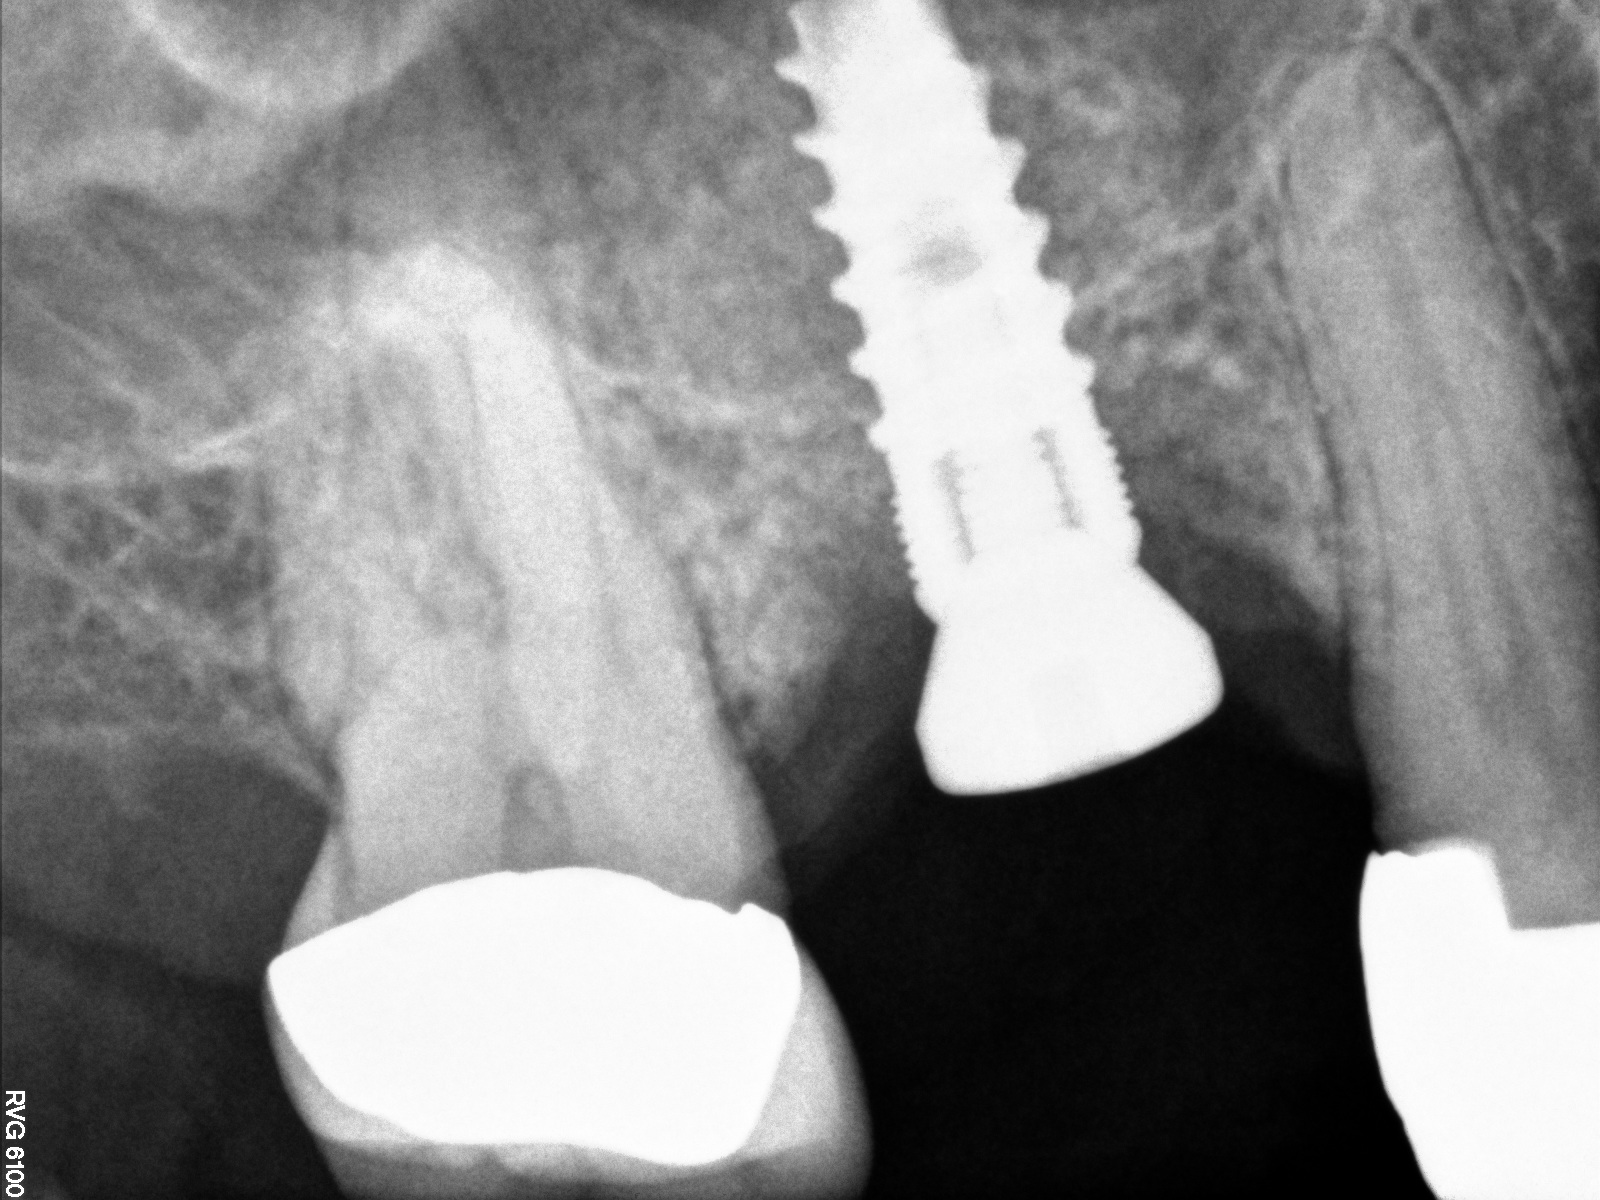

Case 3. Preoperative radiograph showing about 3.5 mm of ridge height.

Fig. 20

Day of sinus augmentation and implant placement in the No. 3 position. The sinus membrane has been raised about 7 mm to 8 mm.

Fig. 21

This patient was a 73-year-old man with only about 3.5 mm of native bone in the No. 3 site (Figure 20). The composite graft used here was a 50:50 mixture of DFDBA and deproteinized bovine bone mineral (Osteohealth, www.osteohealth.com) with approximately 40% calcium sulfate added. The implant was the same type and length as in Case 1 above. Figure 21 shows the area on the day of placement. In the CBCT scan on the day of placement (Figure 22), the native bone and bone graft were clearly discernable. However, the postoperative radiograph taken at 6.5 months (Figure 23) showed no marginal bone loss and a significantly denser appearance than when the graft was place. The membrane was raised about 7 mm to 8 mm. The final radiograph was taken after extraction of tooth No. 2 and after extraction of tooth No. 4 and immediate implant placement.